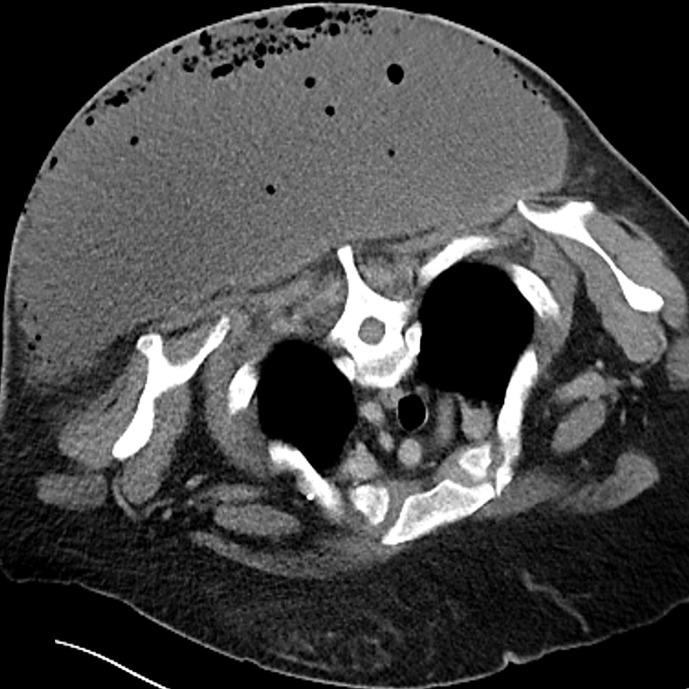

Case presentation: Here, we report the case of a severe subcutaneous abscess on the back caused by F. magna involving an immunocompromised patient with poorly controlled diabetes. A 48-year-old woman with diabetes mellitus and anemia associated with uterine fibroids was referred to us with a 1-month history of a skin manifestation on her back, with a body temperature of 35.9°C and blood pressure of 115/73 mm Hg. The manifestation involved a subcutaneous mass of 36 × 45 cm with a foul odor, partly covered with necrotic tissue, which had the appearance of a tortoiseshell-like pattern. Blood examination revealed C-reactive protein of 21.4 mg/dL and hemoglobin A1c of 9.1%. Contrast-enhanced computed tomography showed a subcutaneous abscess with internal emphysema. Emergency debridement was performed, resulting in drainage of foul-smelling gray-green pus. F. magna was detected in the pus and skin tissue.